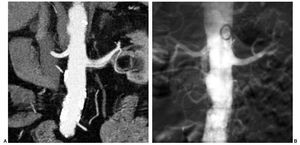

En TCMC se detectaron signos de displasia fibromuscular en tres arterias renales, y fueron clasificadas como estenosis de grado II. Estos hallazgos fueron corroborados tras la realización de la ASD. De los dos pacientes portadores de sendos injertos renales, en uno se diagnosticó correctamente una estenosis de grado III en la anastomosis quirúrgica de la arteria del injerto (fig. 3). En el otro paciente, la arteria del injerto presentaba un aspecto filiforme, en el límite de resolución de la TCMC. Se decidió, por tanto, cotejar su evaluación con la práctica de una ASD en la que se descartó de forma tajante una estenosis significativa potencialmente tratable. También se diagnosticó en la TCMC una disección espontánea de arteria renal, pero sin embargo esta lesión no se confirmó en la ASD (fig. 4). En el resto de casos en los que se detectó patología arterial se consideró la causa ateromatosa como factor etiológico.

Fig. 3. (A) Reconstrucción oblicuo coronal de máxima intensidad de señal centrada en la anastomosis quirúrgica entre la arteria ilíaca y la arteria renal de un injerto renal a nivel pélvico. Estenosis grado III en la arteria del injerto (flecha). (B) Angiografía con sustracción digital (ASD) en la que se demuestra la estenosis preoclusiva en el punto de la anastomosis. (C) En la ASD de control, tras la realización de una APT con balón de 6-20 mm, se aprecia una mínima estenosis residual.